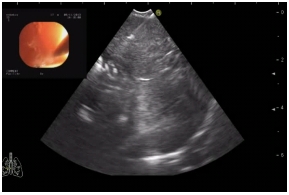

Иллюстрация процедуры EBUS TBNAИллюстрация процедуры EBUS TBNA

Ультразвуковая картина, получаемая при пункции лимфоузлаУльтразвуковая картина, получаемая при пункции лимфоузла